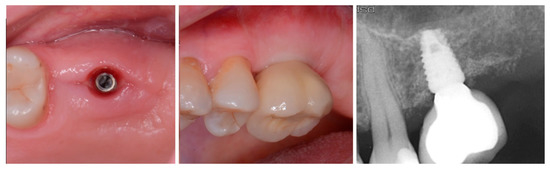

The patient returned at 10 weeks to initiate the restoration of the integrated implant. The implant was exposed, and the cover screw was removed (Figure 6, left). An impression was obtained, and a healing abutment was placed on the site while the restoration was fabricated at the laboratory. Following return of the restoration from the lab, the patient presented. The healing abutment was removed, and a screw-retained restoration was inserted and the screw torque was adjusted to the manufacturer’s recommendation (Figure 6, middle). A periapical radiograph was obtained to verify the seating of the restoration and graft incorporation with the surrounding host bone (Figure 6, right).

Figure 6.

Exposure of the integrated implant after 10 weeks of healing (left). Screw-retained restoration placement (middle) and a radiograph to document seating of the restoration at the implant connector demonstrating conversion of the graft material to host bone (right).

A radiograph obtained at the 2-year recall demonstrated stability of the graft surrounding the implant (Figure 7). The implant and restoration remain in function with no issues reported by the patient or noted at routine recall appointments during the prior period since completion of the restoration.

Figure 7.

Radiograph at 2 years post-restoration placement demonstrating stability and maintenance of the grafted area.